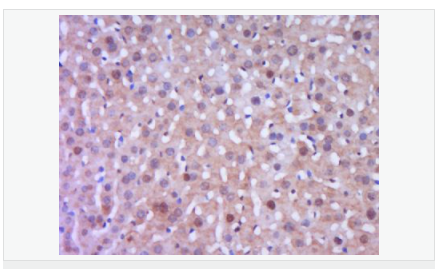

交叉反應(yīng):Human,Mouse,Rat(predicted:Pig,Cow,Rabbit,Sheep) 推薦應(yīng)用:WB,IHC-P,IHC-F,IF,Flow-Cyt,ELISA

| 產(chǎn)品應(yīng)用 | WB=1:500-2000 ELISA=1:5000-10000 IHC-P=1:100-500 IHC-F=1:100-500 Flow-Cyt=1μg/Test ICC=1:100 IF=1:100-500 (石蠟切片需做抗原修復(fù)) not yet tested in other applications. optimal dilutions/concentrations should be determined by the end user. |